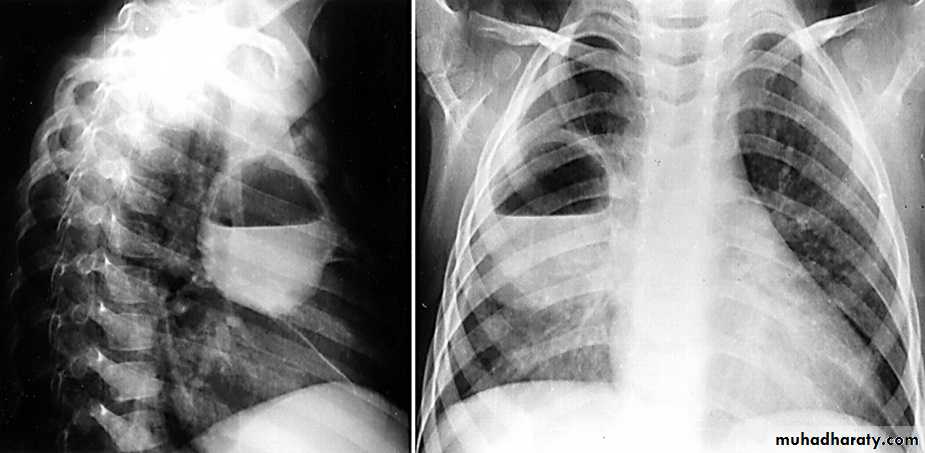

Right middle lobe collapse has distinctive features, and is usually relatively easily identified.

Radiographic features

Chest radiograph

Frontal chest XR showing opasity cause obscuration of the RT cardiac border

Lateral chest XR film the opacity is tongue like shape

versus (triangular in shape) in RT middle lobe consolidation seen in lateral chest XR film

RT lower lobe collapse

usually the medial aspect of the dome of right hemidiaphragm is lost.

the right hilum is depressed

It is important to note that the right heart border, which is contacted by the right middle lobe remains well seen.

Non-specific signs indicating right sided atelectasis may also be present (although due to the small size of the right middle lobe they may well be subtle). They include:

elevation of the hemidiaphragm

crowding of the right sided ribs

shift of the mediastinum to the right